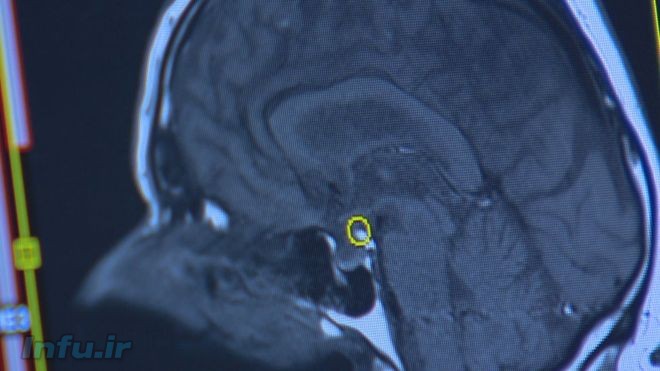

آنها دریافتند که تغییرات ژنتیکی روی قسمتهایی از ارتباطات عصبی مغز تاثیر میگذارد که در تصمیمگیری و شخصیت افراد نقش دارد و آن را کنترل میکند.

پروفسور اندرو مکینتاش، پژوهشگر ارشد این تحقیق در دانشگاه ادینبورگ درباره ارتباط ژنتیک افراد با افسردگی نظر به این مطالعه میگوید: “ما دریافتیم که حدود صد مورد تغییر در دیانای، ساختار ژنتیکی آنها وجود داشت که احتمال دچار شدن آنها به افسردگی را بیشتر میکرد.”